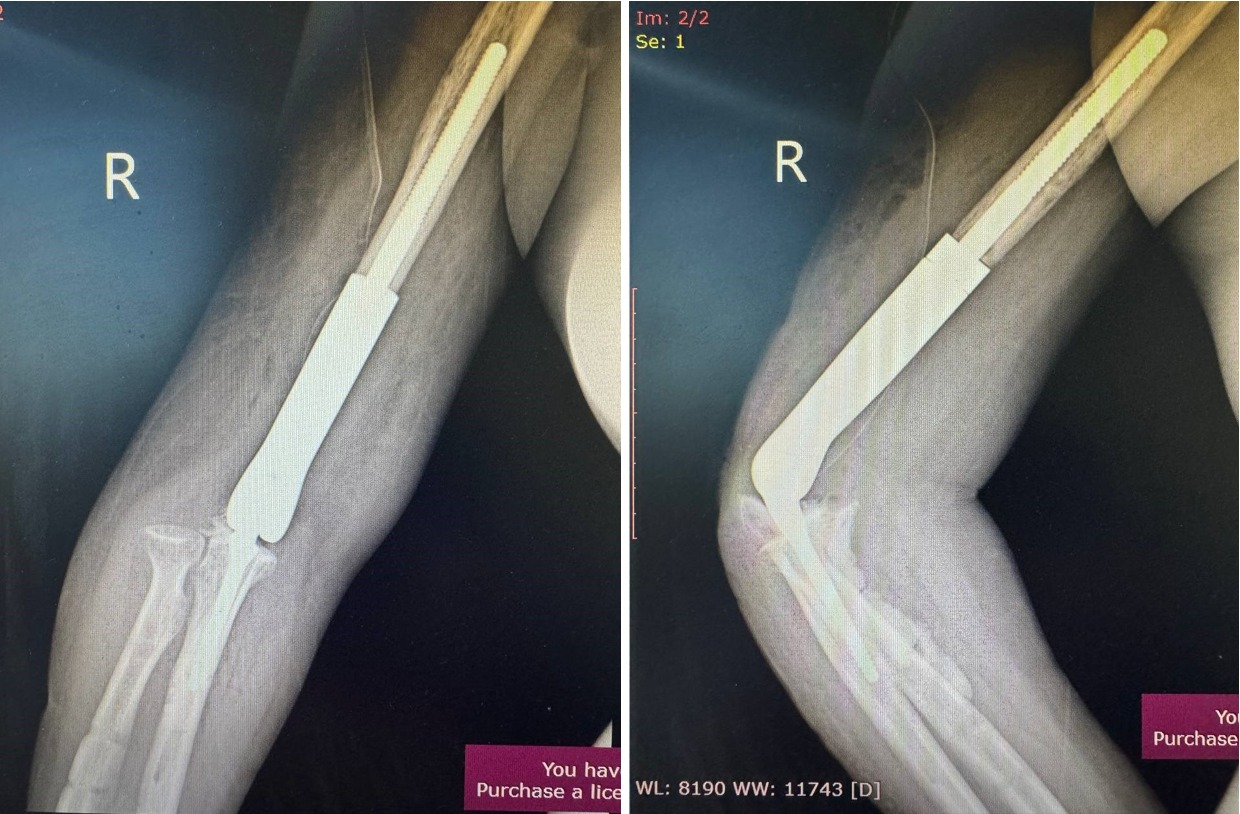

Гэмтэл согог судлалын үндэсний төвийн Гар сарвууны мэс заслын тасгийн эмч нар Монголдоо дахин нэг шинэ төрлийн мэс заслыг амжилттай нэвтрүүллээ. Уг мэс засал нь авто ослын дараах атгаалын чөмөгт ясны доод хэсэг бяцарч, үйрмэг мэт болон хугарч, эргэн сэргэшгүй болж дутмагшил үүссэн (10см орчим) ясыг орлуулах, үеийг орлуулсан, нийлмэл тохойн хиймэл үе бүхий имплантыг суурилуулан гарын хөдөлгөөнийг бүрэн сэргээж, амьдарлын чанарыг сайжруулах мэс засал эмчилгээ юм.

Үйлчлүүлэгчийн биеийн байдал тогтвортой байгаа бөгөөд мэс засал эмчилгээний дараах нөхөн сэргээх эмчилгээнд хамрагдаж байна.